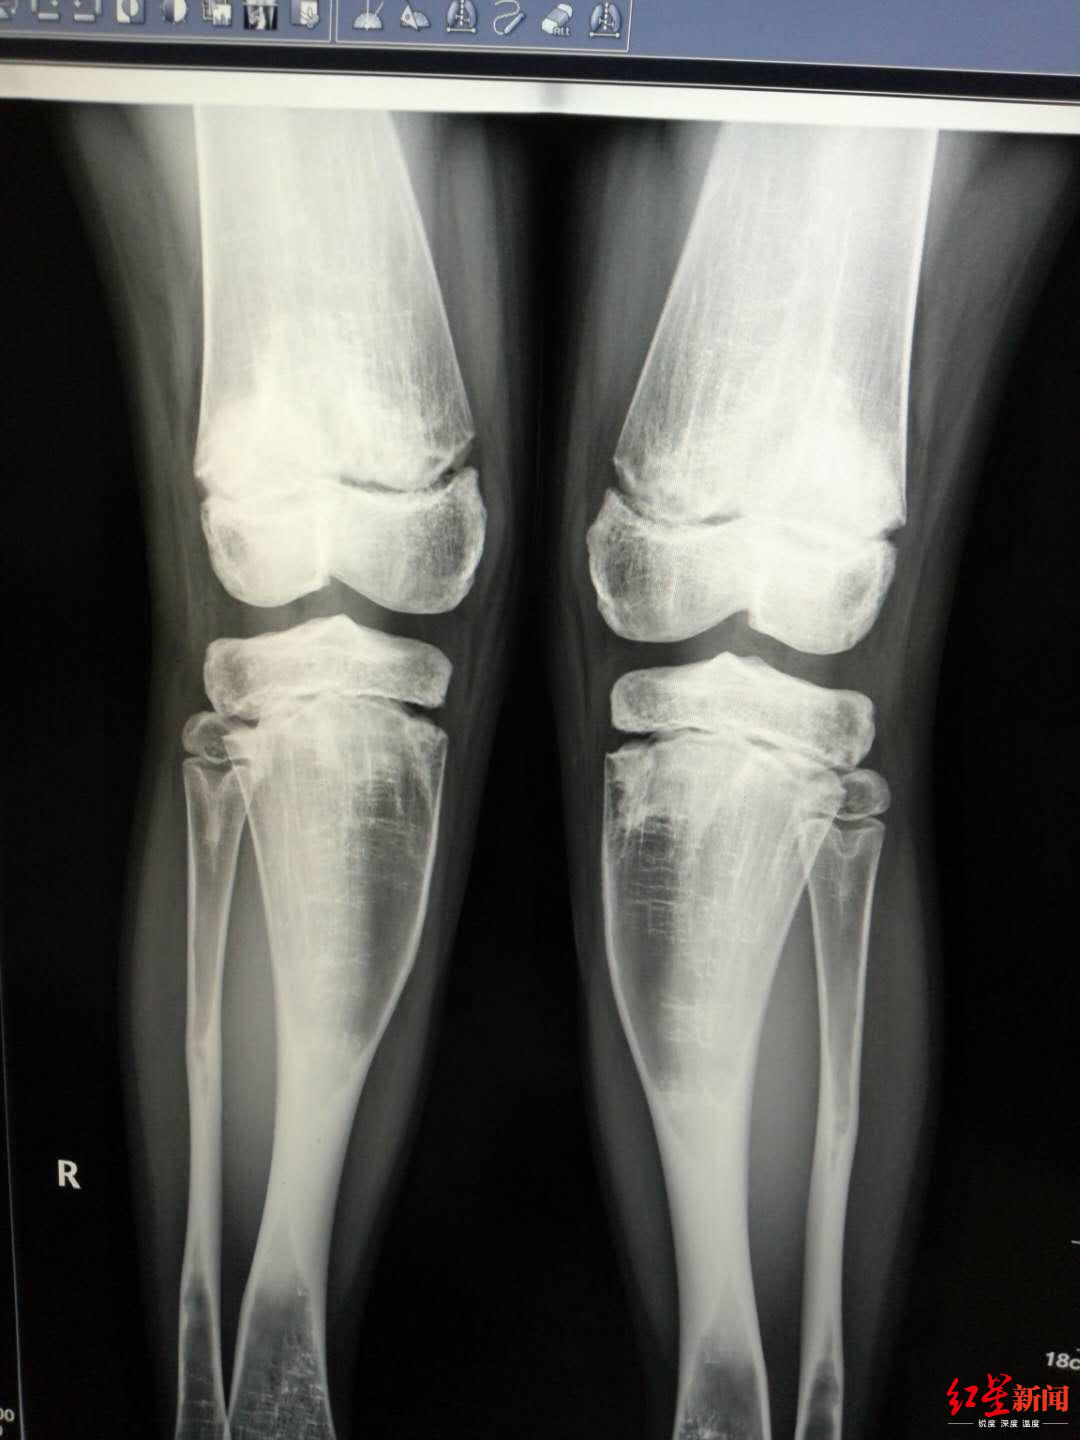

↑小女孩最终被确诊为患有石骨症,患者接受了DR检查。受访者供图

此时已经是7月1日,玄玄住进耳鼻咽喉头颈外科20多天,徐幼马上给玄玄安排了全身DR骨扫描检查,第二天出结果,徐幼第一时间到放射科看片子,结果让她大吃一惊,又反复去看了多次,脑海里蹦出一个词:石骨症。

原来,从片子上看,玄玄从头骨到四肢、到脊椎,全身的骨头都发生的变化,骨质密度增高,骨髓腔闭塞,“正常人,骨髓腔里都是红色的骨髓,有造血的功能,但她的骨头,已经石化改变。”徐幼说,简单地理解,玄玄的骨头,从中空的变成了实心的,像大理石一样。